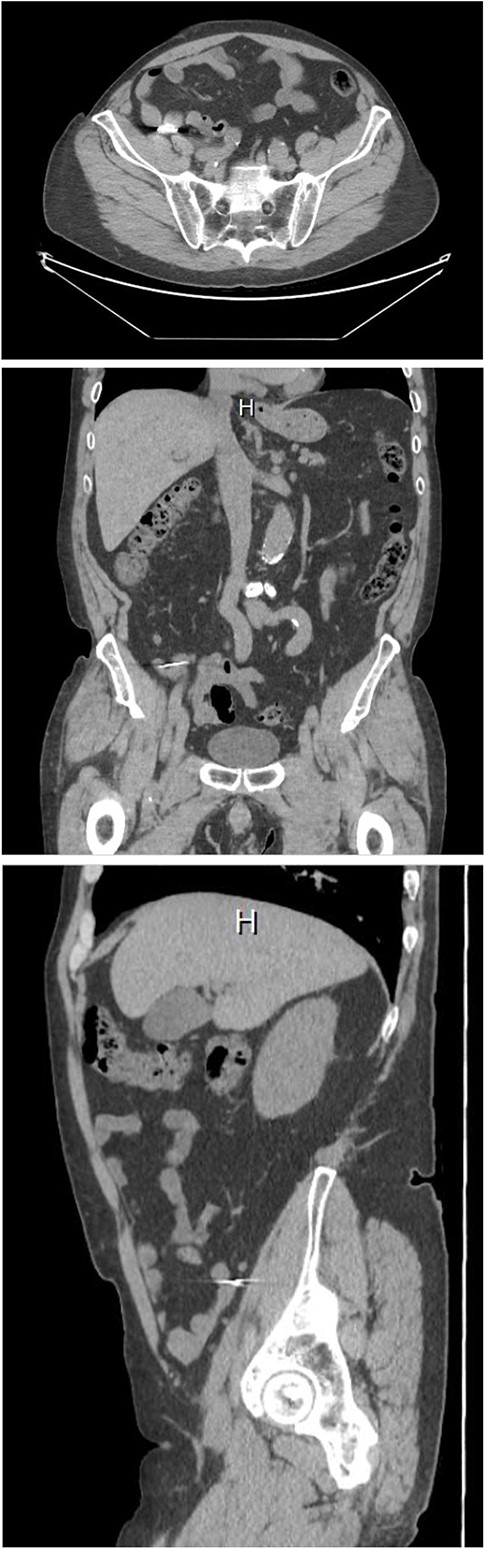

Two weeks after discharge, the patient met with the surgical service and underwent computed tomography (CT) imaging (Fig. 2). Given the negative colonoscopy and these findings on CT, the foreign body was posited to be within the lumen of the appendix. Still, the patient was asymptomatic and regular stool examination was negative for blood or foreign body material. The surgical service recommended that the patient undergo removal of the appendix in accordance with current guidelines to avoid perforation. The appendectomy was scheduled and the patient continued serial abdominal radiographs and bowel regimen in the interim. The preoperative abdominal radiograph taken before the scheduled appendectomy showed absence of the foreign body. The patient admits to recent lapse in examining his stool for presence of the foreign body, and it was assumed that the patient had passed the drill bit.

Computed tomography of the abdomen, axial, coronal, and sagittal views. The foreign body lies over the distal appendix. Detail is limited due to artifact.